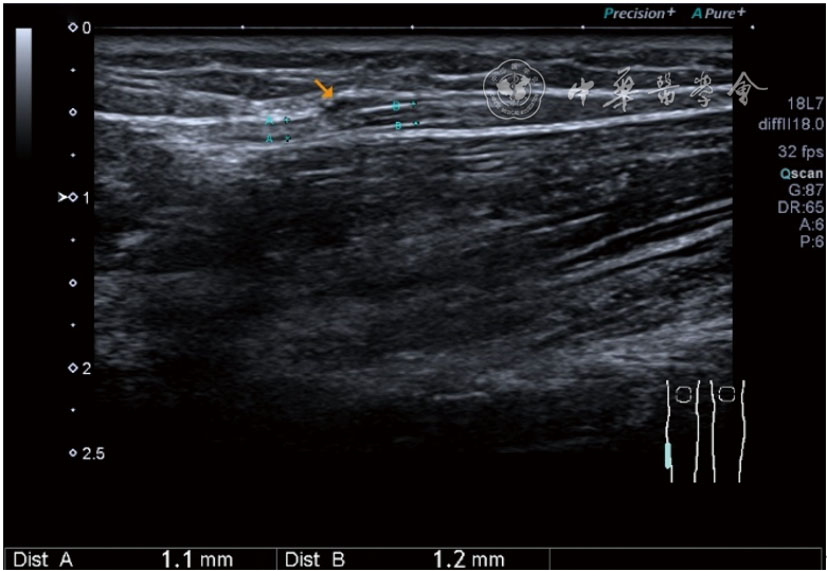

(五)超声影像学表现

患者采取侧卧位,患肢在上,屈膝20°。应用10~18 MHz高频线阵探头,扫查深度1~3 mm。长轴和短轴结合双侧对比扫查。超声影像学所见:短轴可见卡压腓总神经近端增粗,面积增大;长轴可见腓总神经卡压处变细,其近侧肿胀、回声减低,而在卡压远侧则表现正常(图35);一些受压严重者可以出现神经周围积液,卡压神经部位的筋膜增厚(图36);受压神经内血流增加对临床诊断意义更大(图37);探头在病变神经处加压常可引起神经刺激症状。腓总神经支配的肌肉有失神经支配改变,表现为肌肉回声增高和肌肉萎缩(图38)。

图35 超声短轴可见卡压腓总神经近端增粗,面积增大;长轴可见腓总神经卡压处变细,其近侧肿胀、回声减低

图36 超声图像示腓总神经周围积液,卡压神经部位的筋膜增厚